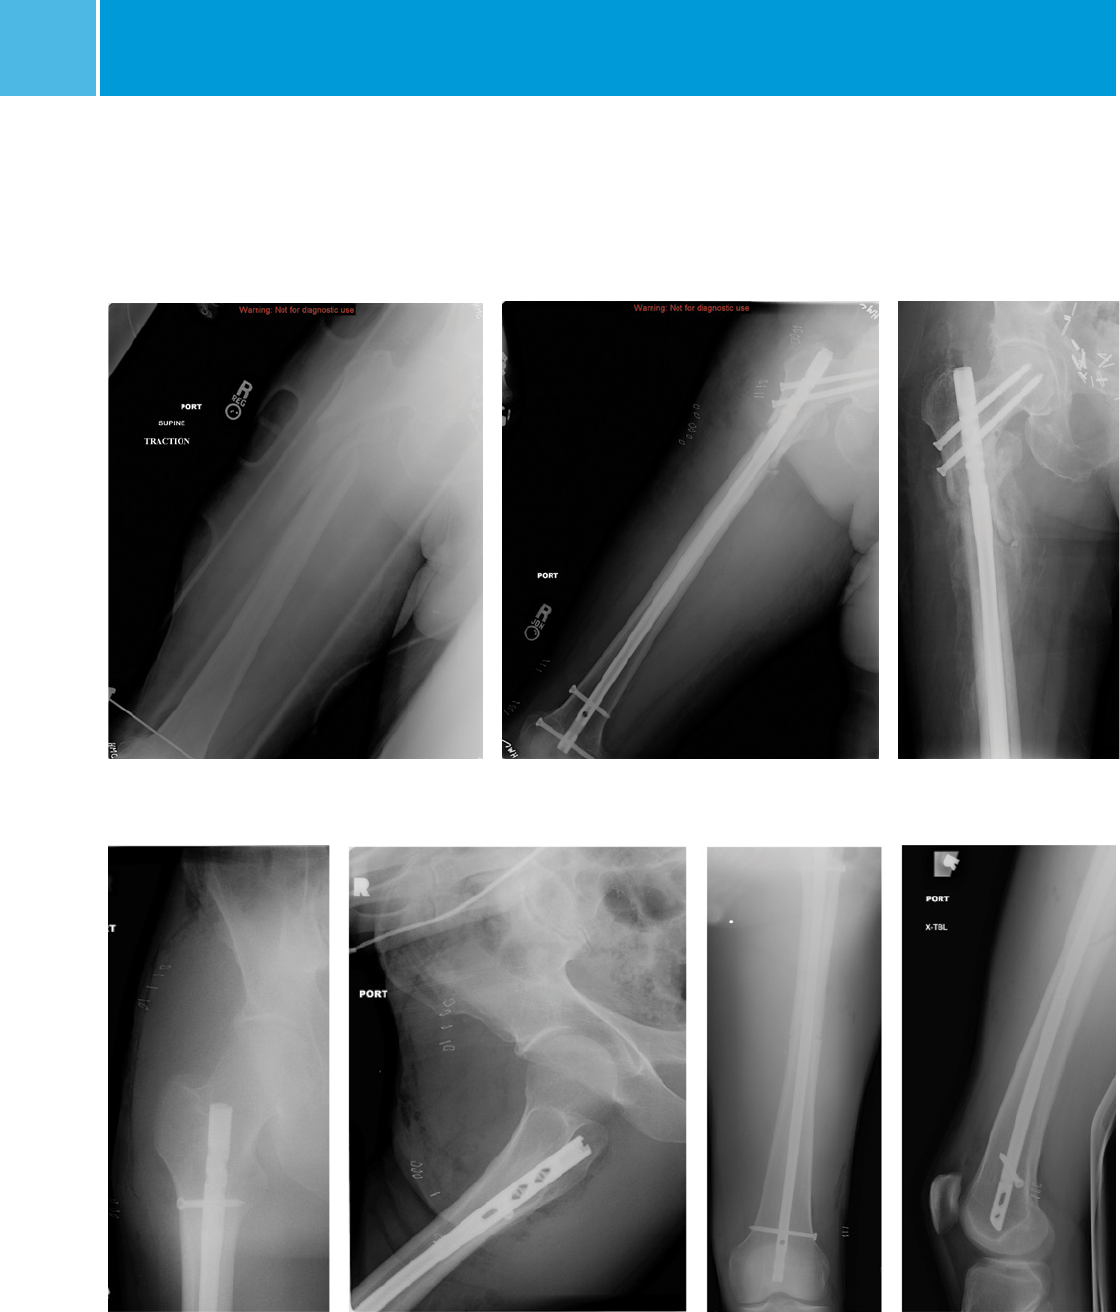

Pre-Op Post-Op

Post-Op

Case Examples